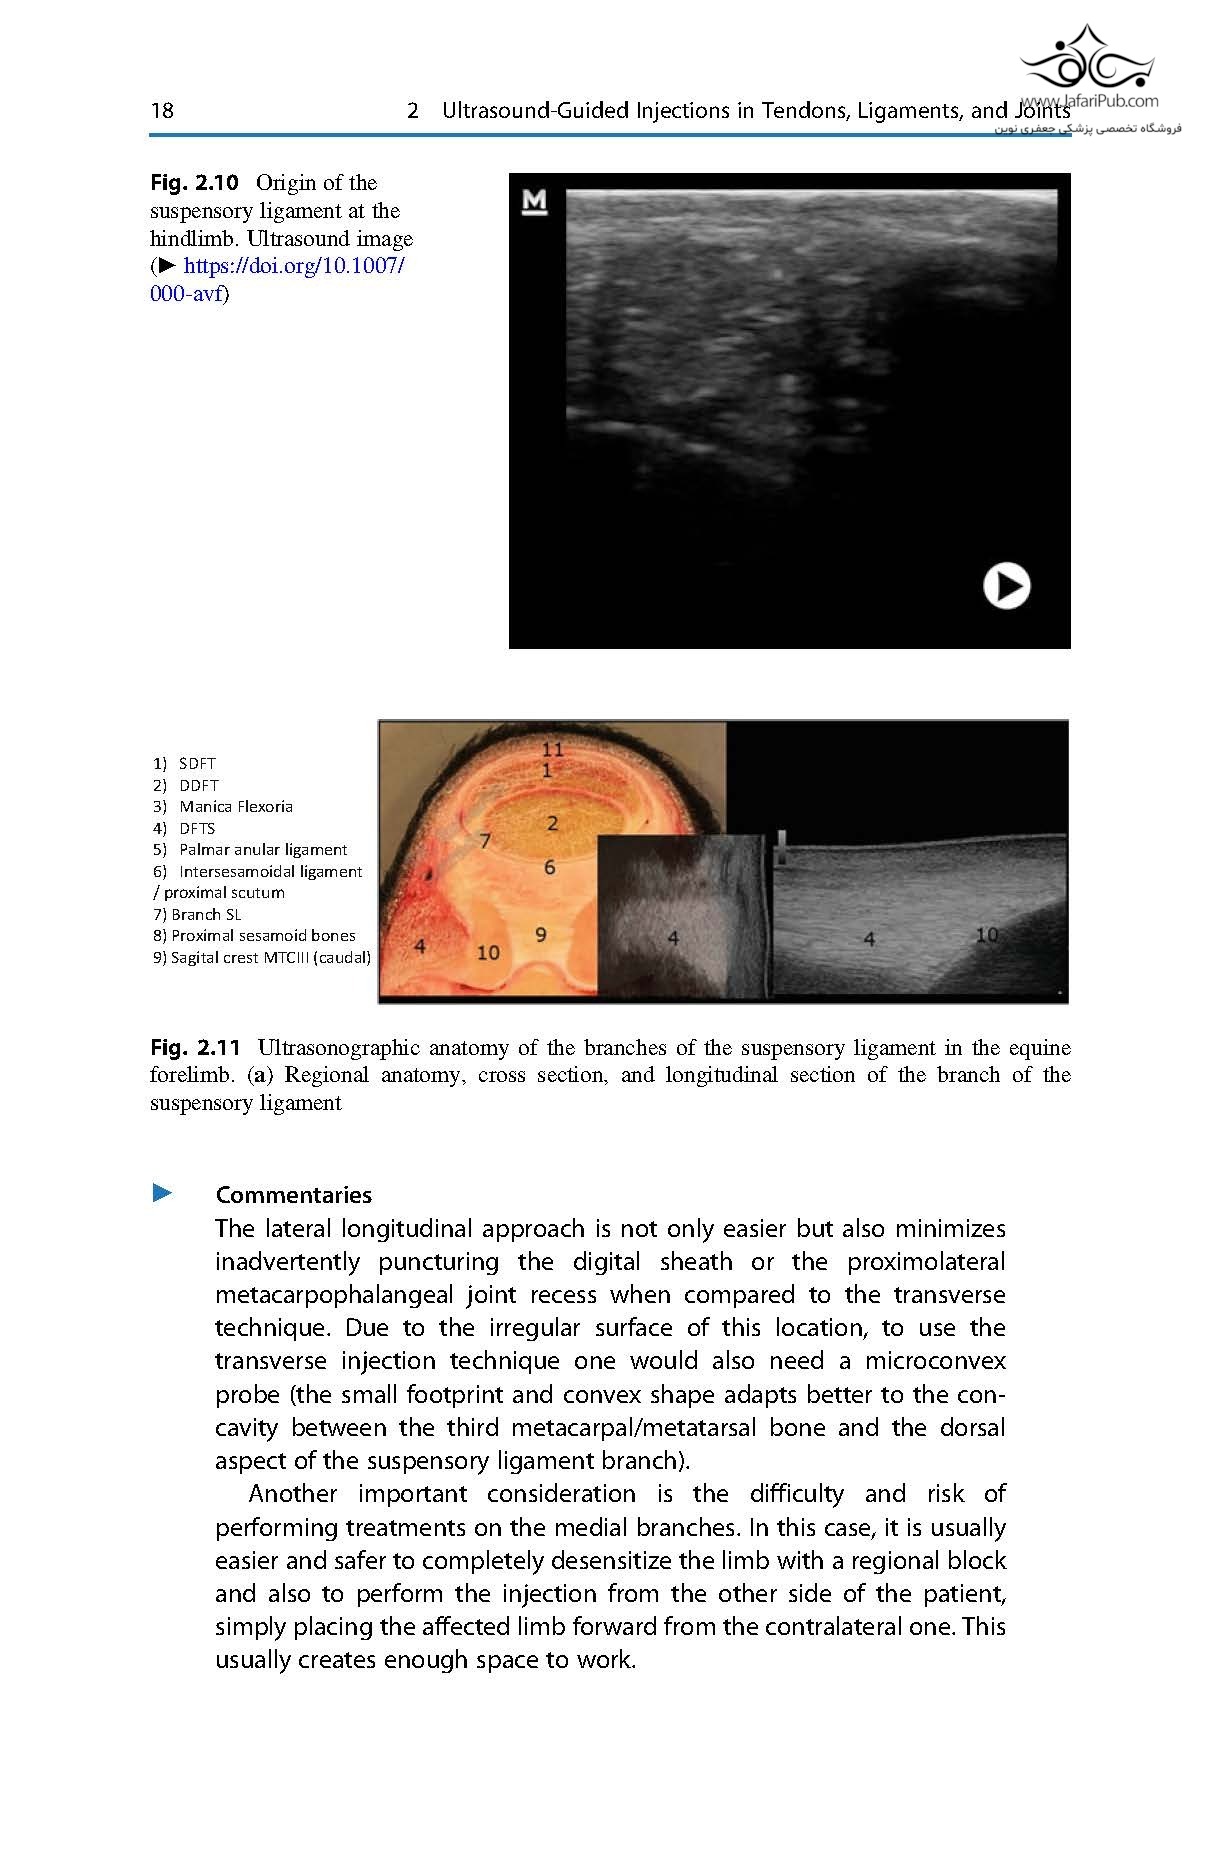

This book serves as a practical guide for equine veterinarians in orthopedics and surgery. It reviews and summarizes the current scientific evidence of the most commonly performed ultrasound-guided procedures for ultrasound-assisted surgery and injections.

For the first time, different techniques are compiled and richly illustrated with pictures and videos to guide the practitioner step-by-step. An initial discussion about the general principles of ultrasound-guided procedures sets the bases for clinicians to understand the general technique and apply it to each approach. Additional chapters describe the most common ultrasound-guided injections in different anatomical structures as well as the surgical approaches that are aided or guided with ultrasound.